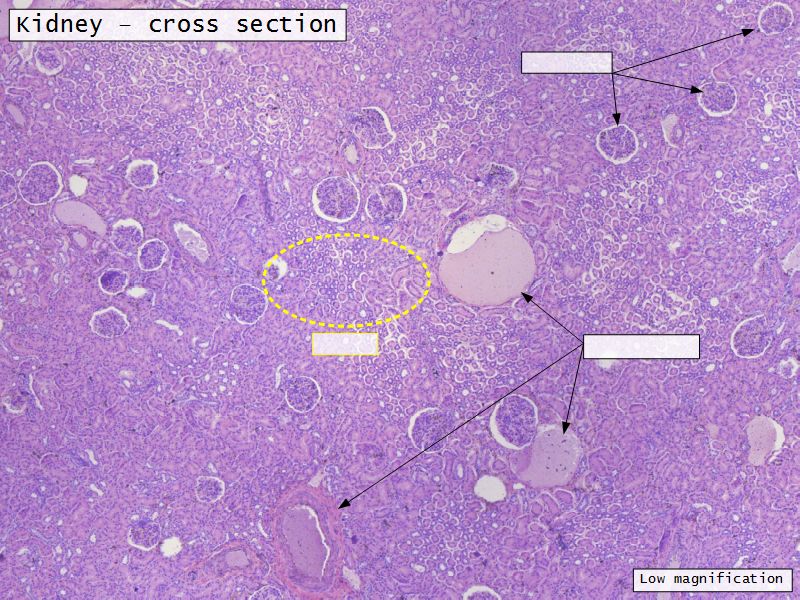

Appearance

• Cortex

• Renal corpuscles

• Convoluted tubules

• Medulla

• Loops of Henle

• Collecting tubules

Kidney lobule

• Group of neprons

• Open into branches

• Same collecting duct

• Not clearly demarcated

• Interlobular arteries/veins